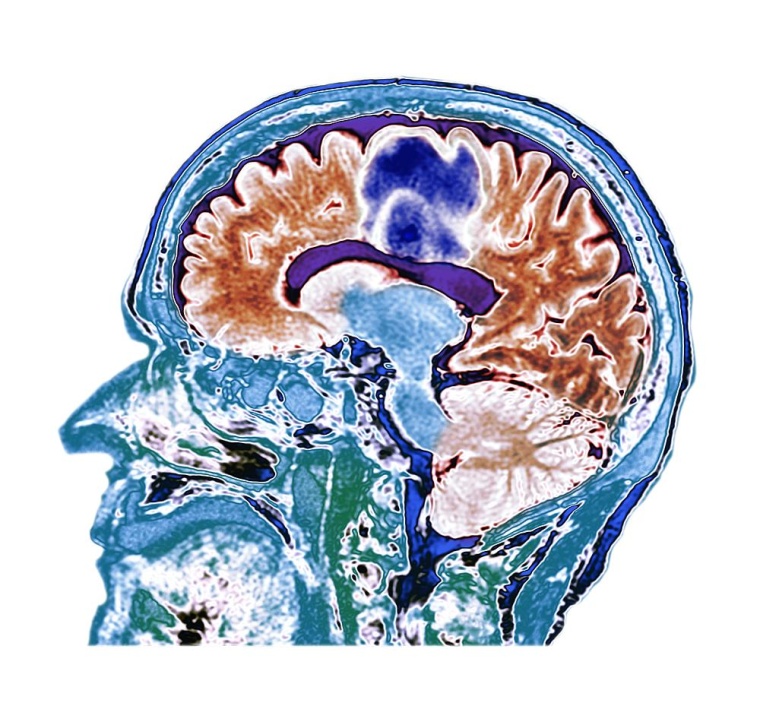

Im klinischen Alltag haben sich die internationalen Diagnosekriterien der UK Parkinson’s Disease Society Brain Bank (1998) und der International Movement Disorder Society (MDS, 2015) bewährt. Sie beruhen jedoch allein auf dem Vorliegen motorischer Symptome sowie dem positiven Ansprechen auf die Dopamin-Vorstufe L-Dopa. „Dabei weist in den letzten 10 Jahren eine zunehmende Zahl gut belegter Studien darauf hin, dass bereits zum Diagnosezeitpunkt die Anzahl nicht motorischer Symptome eine erhebliche Rolle spielt“, erklärte Prof. Dr. med. Claudia Trenkwalder, Leiterin des Kompetenznetzwerks Parkinson und Bewegungsstörungen an der Paracelsus-Elena-Klinik in Kassel sowie Past-Präsidentin der MDS, anlässlich des Deutschen Kongresses für Parkinson und Bewegungsstörungen 2022. Zudem haben neue Erkenntnisse zu potenziellen Biomarkern sowie genetischer Prädisposition und die Optimierung bildgebender Verfahren wie Magnetresonanztomographie wesentlich zur Früherkennung und Prognoseabschätzung beigetragen. „Wir müssen daher die Diagnosekriterien erweitern, um sogenannte Biomarker einzubeziehen und die Variabilität unter den Patientinnen und Patienten zu berücksichtigen.“

Auch spezielle Untersuchungen mit bildgebenden Verfahren wie Magnetresonanztomographie und nuklearmedizinische Methoden können die Diagnose Parkinson bestätigen, ebenso wie molekulargenetische Ansätze. Die Genetik kann eine Diagnose der Erkrankung nicht nur bestätigen, sondern manchmal auch verschiedene Ausprägungsgrade und Verläufe prognostizieren. So wurden aktuell verschiedene Genloki aufgedeckt, die im Zusammenhang mit einem erhöhten Demenzrisiko und Progression bei Parkinson stehen. „Es wird immer deutlicher, dass die Diagnose einer Parkinson-Erkrankung weit über die Einschränkung des Patienten in seiner Beweglichkeit und das Zittern hinausgeht und viele Bereiche der Lebensqualität individuell beeinträchtigt sind. Diagnosekriterien jedoch sollten in einfacher Weise ein komplexes Krankheitsbild unter Berücksichtigung neuer Biomarker für die praktische Anwendung abbilden“, schlussfolgerte Prof. Trenkwalder.